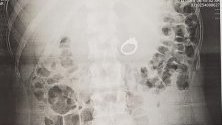

В крайна сметка годеницата била откарана в болница, а от рентгеновата снимка станало ясно, че пръстенът е в стомаха ѝ. Лекарите решили да не рискуват и с помощта на ендоскоп извадили бижуто.